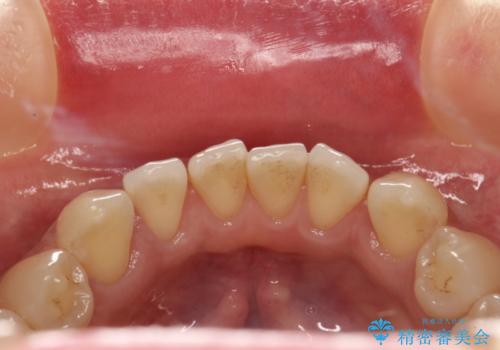

前歯の着色をPMTCできれいに除去

- 前歯の着色が気になるとのことで来院されました。PMTC30分コースを行いました。